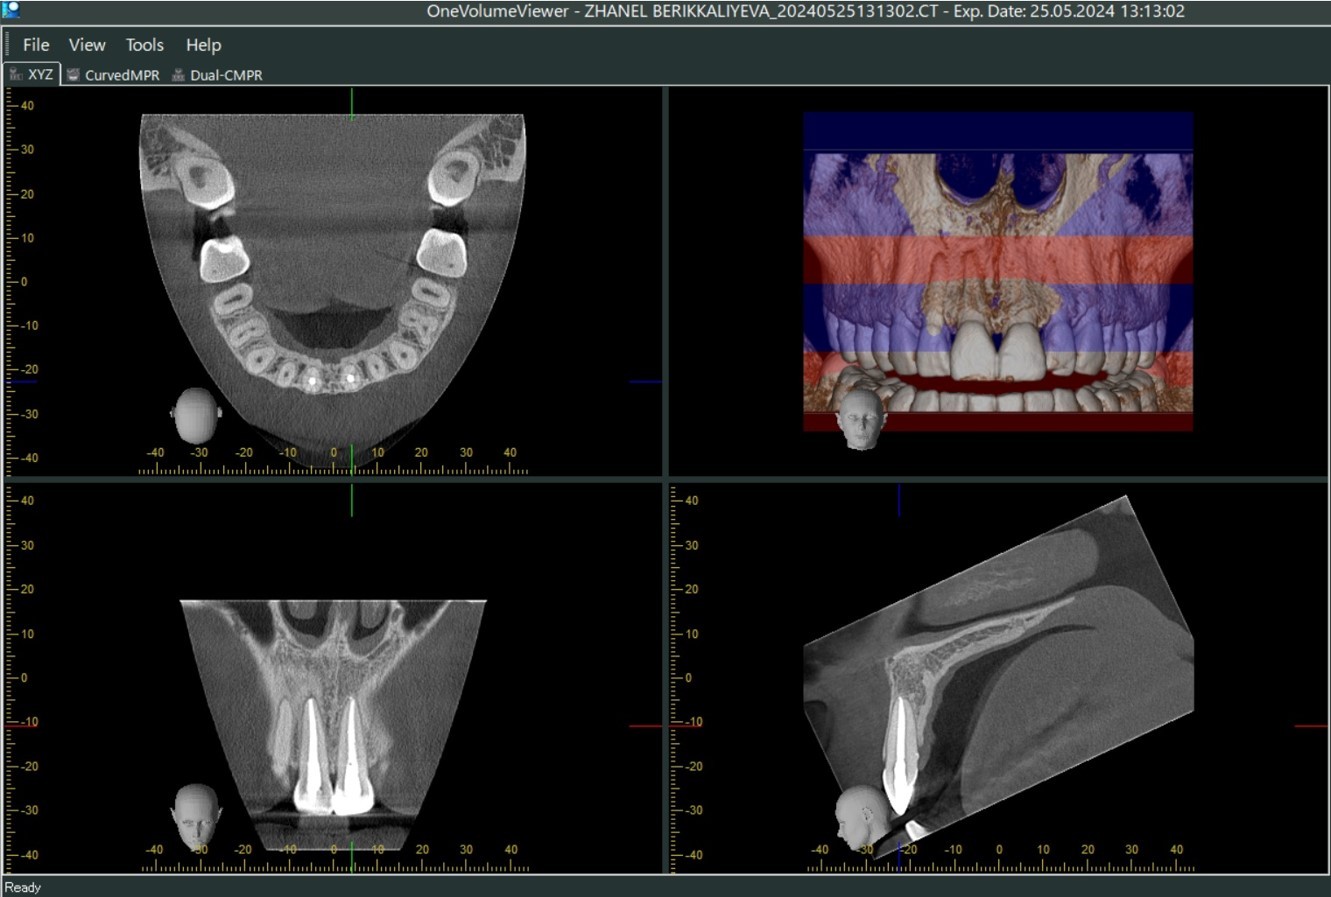

Прицельные снимки и реформаты

КЛКТ после фиксации фрагмента зуба